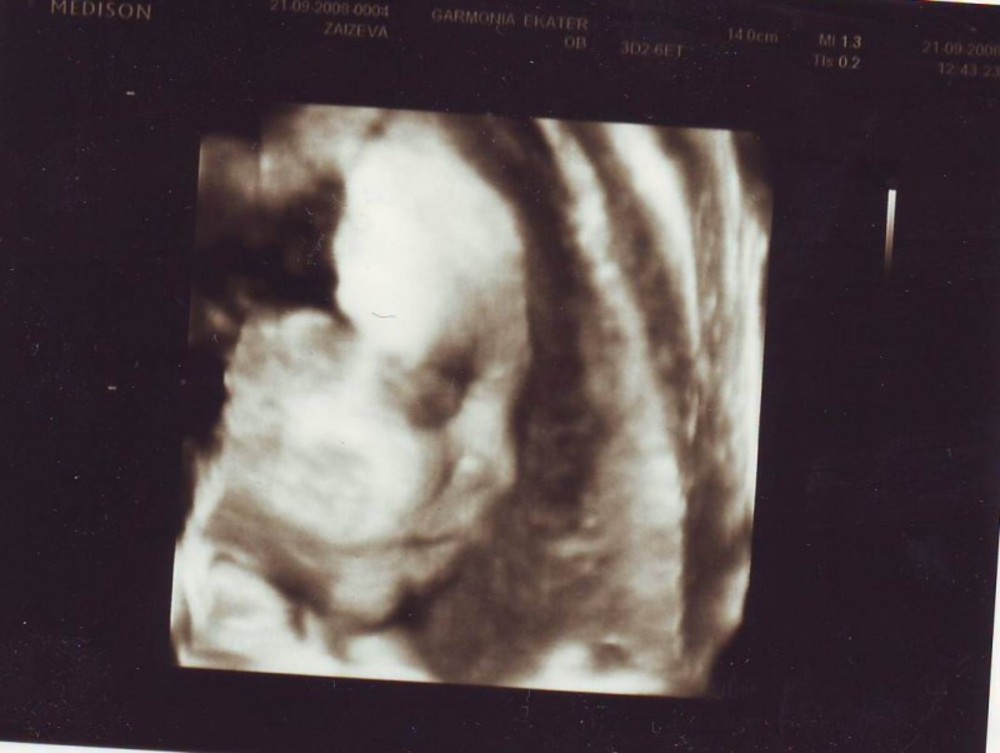

Совет! При проведении ультразвукового исследования могут быть измерены копчиково-теменные размеры плода, на 11 неделе беременности этот показатель составляет около 5 см. Но поскольку рост и развитие ребенка на этом этапе происходит стремительно, то уже через пару недель размеры вашего малыша увеличатся вдвое.

В первый раз рекомендуется проходить скрининг в период с 11 по 16 неделю. Причем врачи рекомендуют пройти это обследование, пока не началась 12 неделя беременности. Дело в том, что в это время хорошо видна воротниковая зона плода, а измерение этой части тела позволяет своевременно выявить наличие риска развития у плода синдрома Дауна.

Будущие мамы должны понимать, что при проведении УЗИ на 11 неделе беременности диагноз не ставят. Проведение скрининга позволяет определить степень риска. То есть, если будут получены результаты, не соответствующие норам, то будущей маме порекомендуют пройти дополнительные экспертные УЗИ и проконсультироваться у врача-генетика.

На сроке одиннадцати недель проводится первый пренатальный скрининг, который направлен на определение пороков развития. Производится ультразвуковое и биохимическое исследование. Первый скрининг направлен не только на выявление пороков развития. Данное обследование позволяет узнать состояние хориона, рост и степень развития плода, точный срок беременности и другие подробности.

Примерно к одиннадцати неделям ваш ребенок официально становится плодом от эмбриона.У вашего ребенка развиваются отчетливые черты лица и гениталии, а сканирование за одиннадцать недель дает захватывающее представление о том, как ваш ребенок растет внутри вас. Сканирование, выполняемое на одиннадцатой неделе, также имеет важное медицинское значение для исключения любых аномалий, синдромов или пороков развития.

Цель 11-недельного ультразвукового исследования

Сканирование беременности в первом триместре всегда особенное, так как оно дает представление о развивающемся ребенке. Сканирование на 11-й неделе дает вам возможность впервые увидеть, как выглядит ваш ребенок.Это также самая ранняя стадия, на которой врач может обнаружить у ребенка определенные аномалии. У сканирования на 11-й неделе много разных целей. Вот несколько причин, по которым нельзя пропустить 11-недельное сканирование.

- Во время 11-недельного сканирования плод проверяется на хромосомные аномалии, такие как синдром Дауна. Результаты сканирования оцениваются вместе с результатами анализа крови для постановки диагноза.

- Плотность затылочной кости (NT), измеряемая как полупрозрачное пространство в ткани под шеей плода, используется в качестве фактора оценки риска синдрома. Прозрачность затылочной кости также используется в качестве ориентира для исключения любых врожденных сердечных заболеваний.

- Гестационный возраст ребенка проверяется по росту плода.

УЗИ в первом триместре на одиннадцатой неделе обычно представляет собой простую процедуру, которая занимает около нескольких минут.Опытный сонограф довольно легко измеряет прозрачность затылочной части. Они также проверяют другие жизненно важные параметры роста, такие как длина темени и крестца, диаметр гестационного мешка, положение и размер плаценты и т. Д. Положение плода может замедлить время, необходимое для сканирования. Иногда ребенок может быть повернут набок или свернут клубочком, что затрудняет измерение ткани ниже шеи. Обычно сонографист предлагает повторить сканирование через некоторое время, пока не будет установлено правильное положение плода.

Сканирование на 11 неделе обычно выполняется трансабдоминально.

На нижнюю часть живота наносится охлаждающий гель, а преобразователь, который посылает ультразвуковые волны в матку, перемещается по животу, чтобы обеспечить четкое изображение плода. Изображения ребенка делаются сверху и по бокам, чтобы лучше видеть все внутренние и внешние органы.

Что можно увидеть на сканированном изображении?

Многие матери с тревогой относятся к 11-недельному УЗИ.Хотя это очень важное сканирование, которое исключает любые отклонения от нормы у плода, не стоит паниковать. Вероятно, это первый раз, когда вы видите движущегося ребенка, поэтому будьте готовы к сильному волнению.

Ребенок в 11 недель выглядит более человечным, с хорошо сформированными руками и конечностями. На этом этапе у вашего ребенка хорошо развиты голова и кости. Тело все еще непропорционально, с большой головой и сравнительно маленьким туловищем. Вы можете поймать подпрыгивающего ребенка и ударить его по водянистому амниотическому мешку.На этой неделе начинают формироваться половые органы ребенка, которые могут быть нечетко видны на снимке. Ваш сонографист, возможно, не сможет сделать вывод о поле ребенка на данном этапе. Плод на этой стадии имеет длину всего один-два дюйма, но имеет быстро развивающуюся систему органов.